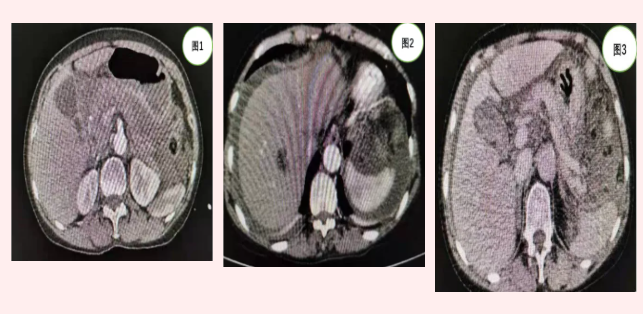

患者張某入院時(shí),急診行全腹CT(見圖1)等相關(guān)檢查發(fā)現(xiàn)上腹部包塊但未見明顯肝脾破裂及腹腔積液。由于患者外傷,病情隨時(shí)可能加重,主管醫(yī)師張浩杰嚴(yán)密觀察病情時(shí),患者腹痛加重,血紅蛋白進(jìn)行性下降,立即復(fù)查上腹部增強(qiáng)CT(見圖2、3)發(fā)現(xiàn)腹腔大量積液。